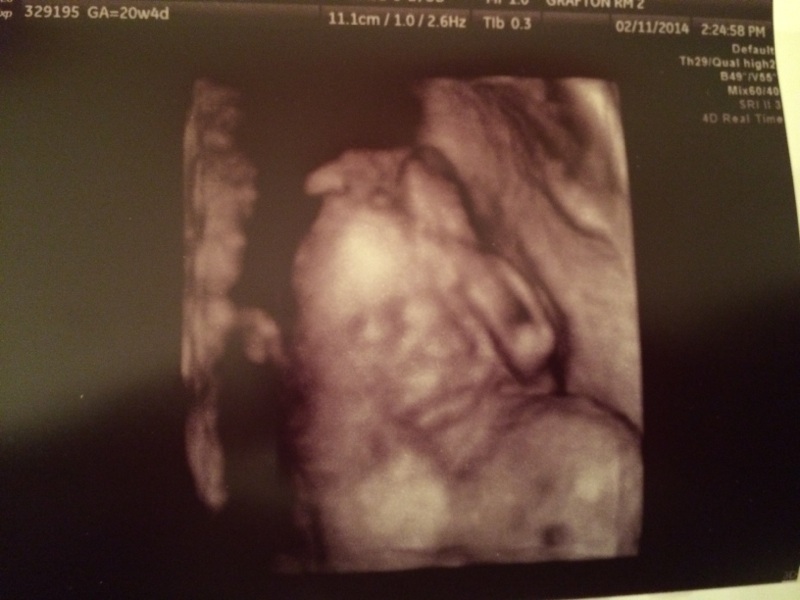

Mini hand by the sweet face profile.

Another profile shot!

3D Ultrasound Face Pic! This one is my second fave. Smooshy pout face.

My favorite little face pic. She’s just so precious with her little hand up by her face. I can’t wait to kiss that little face.